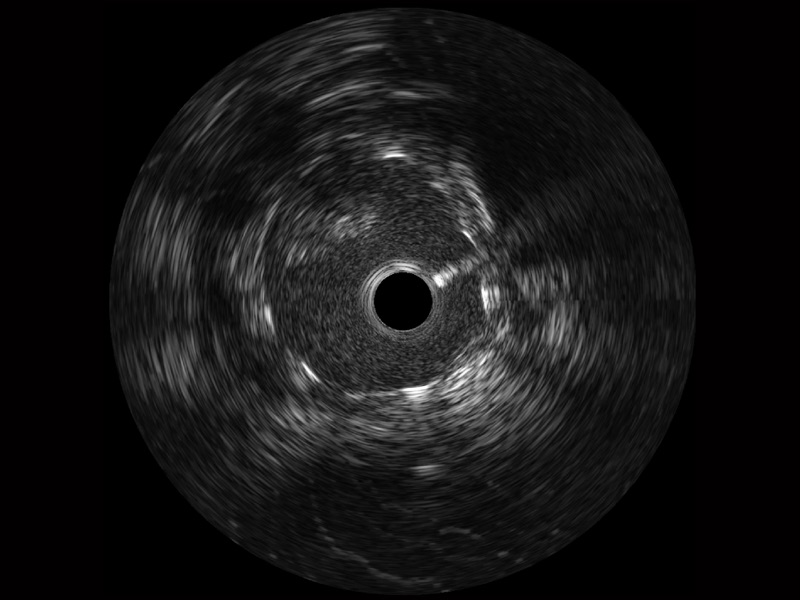

開立寬頻IVUS圖像

傳統(tǒng)IVUS圖像

對比傳統(tǒng)IVUS導管成像,開立寬頻IVUS圖像的近場支架梁顯影更細膩,遠場中膜外血管仍清晰可辨,兼顧遠中近,兼顧分辨力與穿透深度